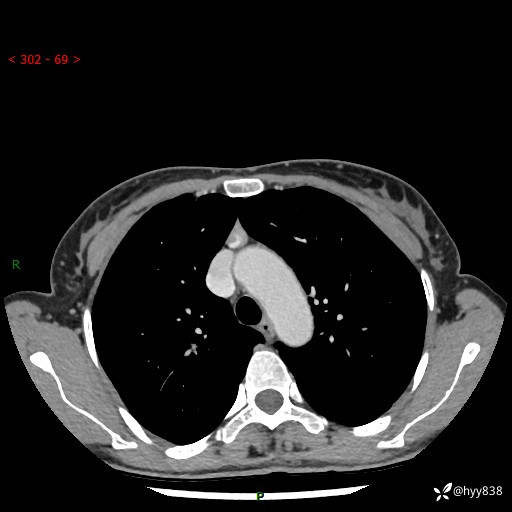

增强动脉期+静脉期